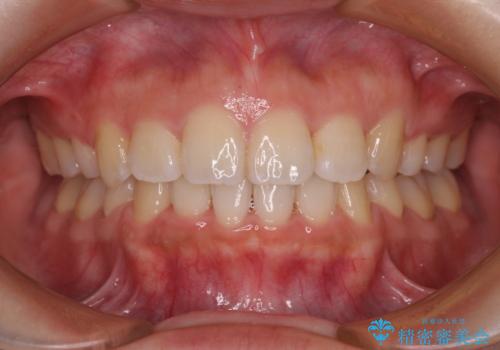

4本の歯を抜歯したことで、飛び出していた口元が引っ込み、横顔の印象が大きく改善されました。